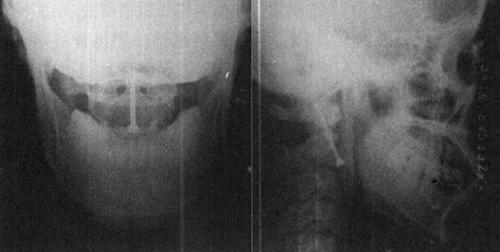

图13-12 42岁女性,C5~C6脱位,前路CSLP固定